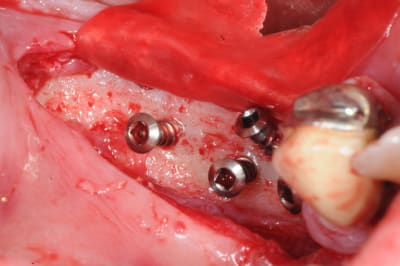

Tu veux dire une crête comme ça?

--

xbk

"Si tous ceux qui croient avoir raison n'avaient pas tort, la vérité ne serait pas loin" Dac Pierre